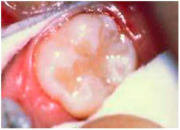

| 08:55, 18 ביוני 2013 | איטומי חריצים2.png (קובץ) |  |

105 קילו־בייטים | Motyk | 1 | |

| 08:48, 18 ביוני 2013 | איטומי חריצים1.png (קובץ) |  |

194 קילו־בייטים | Motyk | 1 | |